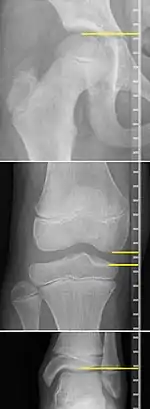

X-rays for leg length measurement.

On X-rays, there is generally measurement of both the femur and the tibia, as well as both combined.[4] Various measuring points for these have been suggested, but a functional method is to measure the distances between joint surfaces:[4]

• Femur length: The superior aspect of the femoral head and the distal portion of the medial femoral condyle.

• Tibial length: The medial tibial plateau and the tibial plafond